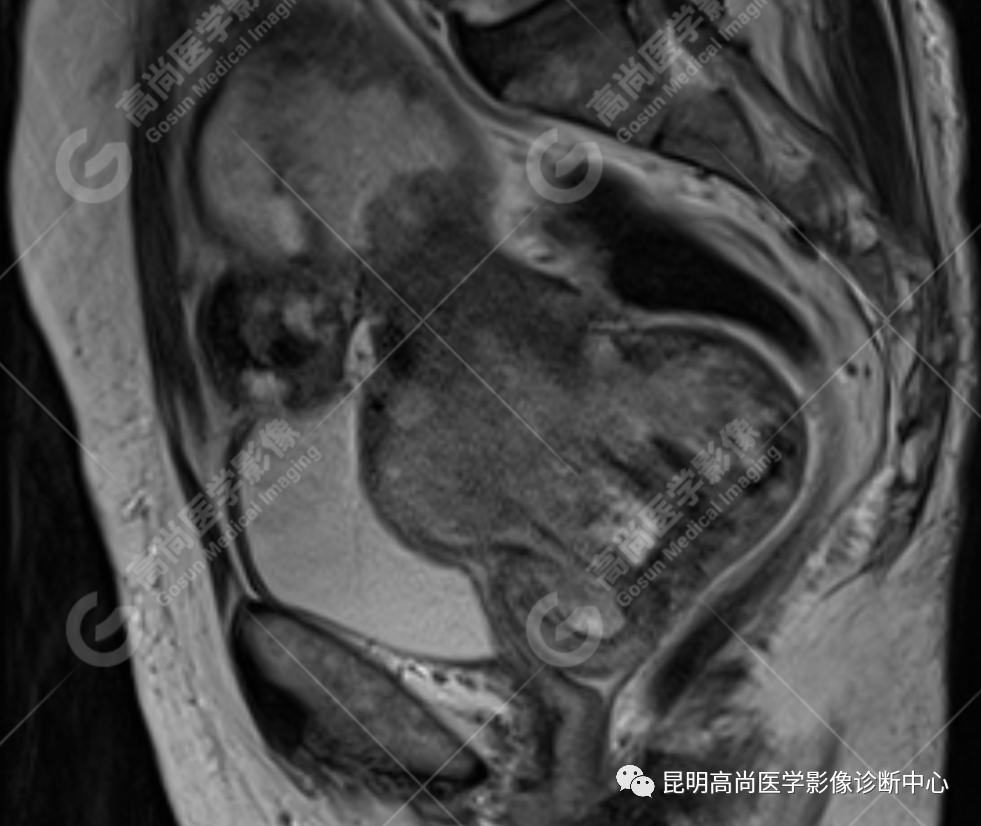

影像诊断

子宫、附件未见显示;下腹部及盆腔内巨大占位,考虑恶性肿瘤,肉瘤可能,阴道及肛管受侵,建议活检。

MRI 表现

不规则菜花状或息肉状肿物,子宫内膜正常 T2WI 清晰连续的高信号消失,取而代之是中高、高信号,不均匀混杂信号,信号强度低于内膜正常信号强度,T1WI 上内膜信号增高,子宫肌层明显变薄,未受侵者肌层信号均匀,因肿物组织来源不同,病变信号复杂,以 T2WI 表现为等高混杂信号为主。因病灶较大,可合并囊变坏死及肿瘤出血。

肌层到肿块内的血管流空信号,可提示肿瘤内有血供丰富的肉瘤成分,血管流空信号在子宫内膜癌中未见报道,但在子宫平滑肌瘤、平滑肌肉瘤中可见。